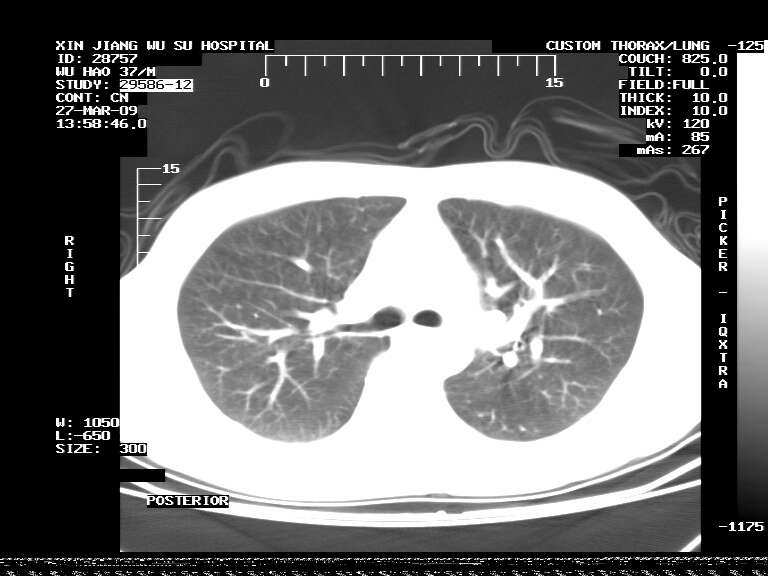

男,37岁,体检胸透发现阴影。

患者体检发现 无症状 左肺下叶占位,边缘模糊,可见血管聚束、分叶、胸膜牵拉,增强呈不均匀性强化。 首先考虑左肺下叶周围型肺癌,建议穿刺活检。

患者体检发现 无症状 左肺下叶占位,边缘模糊,可见血管聚束、分叶、胸膜牵拉,增强呈不均匀性强化。 首先考虑左肺下叶周围型肺癌,建议穿刺活检。支持!

左肺下叶见一结节病变,边缘欠清不光滑,与胸膜粘连且胸膜局限性增厚,注药后呈环形强化,动脉期壁呈明显点环状强化,静脉期壁强化减低,中心密度低无强化,灶周无明显的卫星灶和水肿区(晕征)---考虑周围性肺癌,不除外感染性病变,建议穿刺活检。